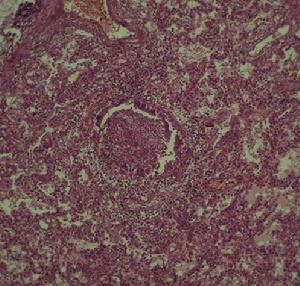

沙雷菌肺炎2.培養與生化反應沙雷菌對生長的培養基要求不高。在營養瓊脂、遠藤瓊脂,麥康凱瓊脂、血瓊脂平板上均可生長。黏質沙雷菌菌落圓形,略呈粗糙有黏性。在低於37℃的溫度培養時,鞭毛較易發育。為需氧或兼性厭氧菌。沙雷菌能發酵葡萄糖,但只有部分菌株產生少量氣體。不發酵乳糖、衛矛糖、阿拉伯糖、棉子糖及鼠李糖,可發酵甘露醇、水楊苷及山梨醇,對側金盞花醇及肌醇發酵力不一致。不形成吲哚,大部分菌株甲基紅反應為陰性,在氰化鉀培養基內生長。大部分菌株迅速液化明膠,少數為遲緩反應。具有賴氨酸和鳥氨酸脫羧酶。但不形成精氨酸雙水解酶及苯丙氨酸脫氨酶,不利用丙二酸鈉,能利用枸櫞酸鹽,VP反應陽性,在三糖鐵培養基上(TSI)產酸不產氣。能產生細胞外DNA酶,脂肪酶。沙雷菌產生紅色色素,在低於37℃培養時,色素產生往往更豐富,但多次傳代後產生色素的能力減弱,甚至消失。1902年Kroft提取該色素並命名為“靈菌紅素”(prodigiosin),因而黏質沙雷菌過去稱為靈桿菌。直到1960年才被Rapoport和Hollen闡明其化學結構。靈菌紅色素溶於酒精、乙醚、氯仿等有機溶劑,不溶於水。靈紅菌素是一種脂多糖,有報導它具有提高白細胞數量和消炎作用。產生色素與不產生色素菌株均可致病,可引起敗血症、尿道及呼吸道感染,骨髓炎及術後傷口感染。

3.抗原與分型沙雷菌有菌體“O”抗原和鞭毛“H”抗原。現已知有15種O和13種H,共46個血清型。